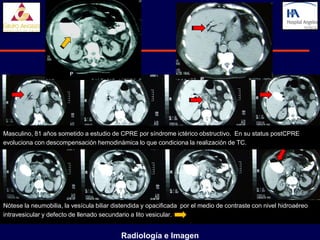

Masculino, 81 años sometido a estudio de CPRE por síndrome ictérico obstructivo. En su status postCPRE

evoluciona con descompensación hemodinámica lo que condiciona la realización de TC.

Nótese la neumobilia, la vesícula biliar distendida y opacificada por el medio de contraste con nivel hidroaéreo

intravesicular y defecto de llenado secundario a lito vesicular.